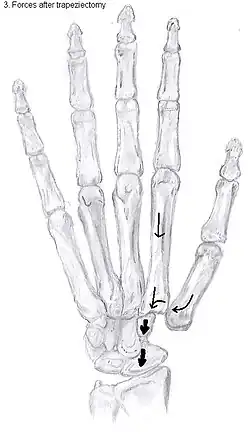

An empty gap is left by the trapeziectomy and the wound is closed with sutures. Despite this gap, no significant changes in function of the thumb are reported.[27] After the surgery, the thumb will be immobilized with a cast.

Some physicians still believe that it is better to fill the gap left by the trapeziectomy. They assume that filling the gap with a part of a tendon is preferable in terms of function, stability and position of the thumb. This is based on the assumption that interposition can help maintain the space between the metacarpal and the scaphoid, which will improve comfort and capability. Neither of these assumptions is supported by experimental evidence.

Trapeziectomy with ligament reconstruction

Another technique is used to reconstruct the volar beak ligament after trapeziectomy. The rationale is that ligament reconstruction(LR) helps maintain the gap between the metacarpal and the scaphoid, and that a larger gap is associated with greater comfort and capability.[32] Again these possibilities are not supported by experimental evidence.

Trapeziectomy with LRTI

Some physicians believe that combining LR with TI will help maintain gap between the metacarpal and the scaphoid.[33] And that doing so will improve comfort and capability. Keep in mind that these aspects of the rationale are not supported by experimental evidence. The evidence suggests that all of these procedures have comparable long-term results.